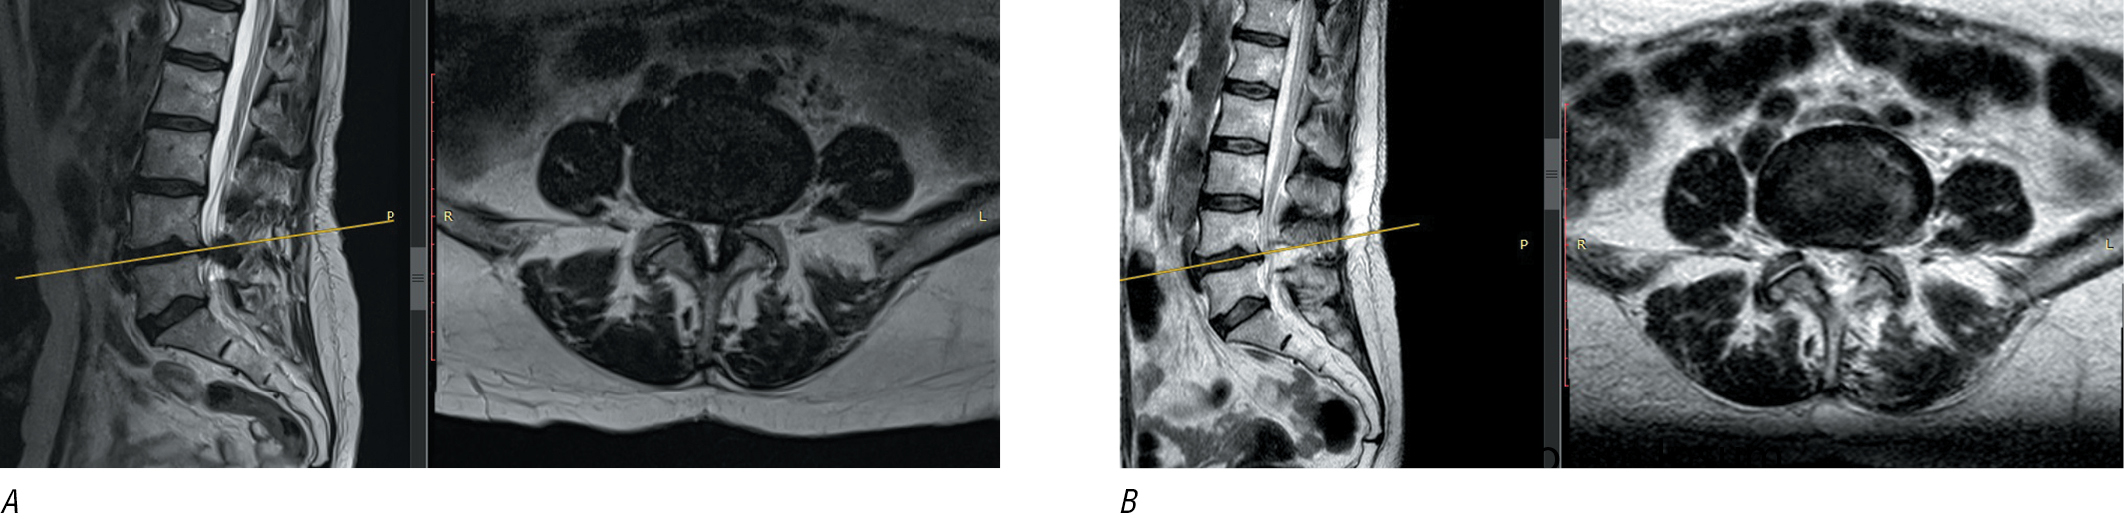

For surgical treatment of central stenosis formed by hypertrophic joints and the yellow ligament and stenosis of the lateral recess, there are percutaneous endoscopic systems with a 10-mm port, which allow adequate decompression even with severe compression of the nerve structures. Through unilateral access, decompression is carried out on one side of the SC and on the opposite side using the over-the-top technique (Fig. 6, 7).

Fig. 7. MRI of a patient with central degenerative stenosis at L4–L5 level. А, before surgery; В, after endoscopic decompressoin with DeltaJoimax.

A pilot, multicenter, randomized, double-blind study (2020) compared two minimally invasive approaches in the treatment of lumbar spinal stenosis: uniportal full-endoscopic interlaminar and tubular approaches [40]. The only significant difference found was a better improvement in Oswestry Disability Index (ODI) (i.e. in functional status) at 6 months in endoscopic group. All patients underwent MRI before and after surgery. Between-group differences were not statistically significant. Finally, clinical improvement was shown to be independent of the degree of increase in the cross-sectional area of the SC or dural sac. There were statistically significant between-group differences in intraoperative blood loss (lower in endoscopic group), while number of complications was similar in both groups (2 in each group).